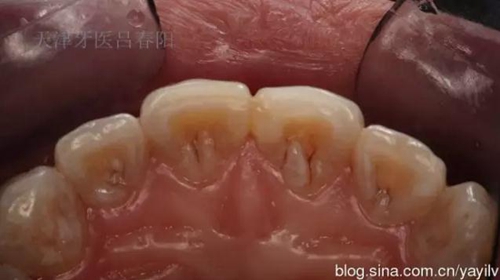

前牙齲洞的美學(xué)樹脂充填修復(fù) 科貿(mào)嘉友收錄

發(fā)一個最近完成的病例吧,雖然齲洞不大,但是挺好玩的,我自己認為。